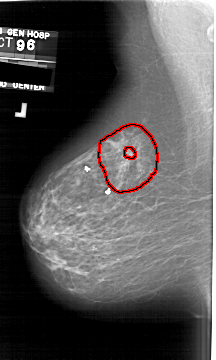

A_1628_1.LEFT_MLO

LEFT_MLO LINES 6466 PIXELS_PER_LINE 3871 BITS_PER_PIXEL 12 RESOLUTION 43.5 OVERLAY

FILE: A_1628_1.LEFT_MLO.OVERLAY

TOTAL_ABNORMALITIES 1

ABNORMALITY 1

LESION_TYPE MASS SHAPE ARCHITECTURAL_DISTORTION MARGINS SPICULATED

ASSESSMENT 5

SUBTLETY 5

PATHOLOGY MALIGNANT

TOTAL_OUTLINES 2

BOUNDARY

CORE